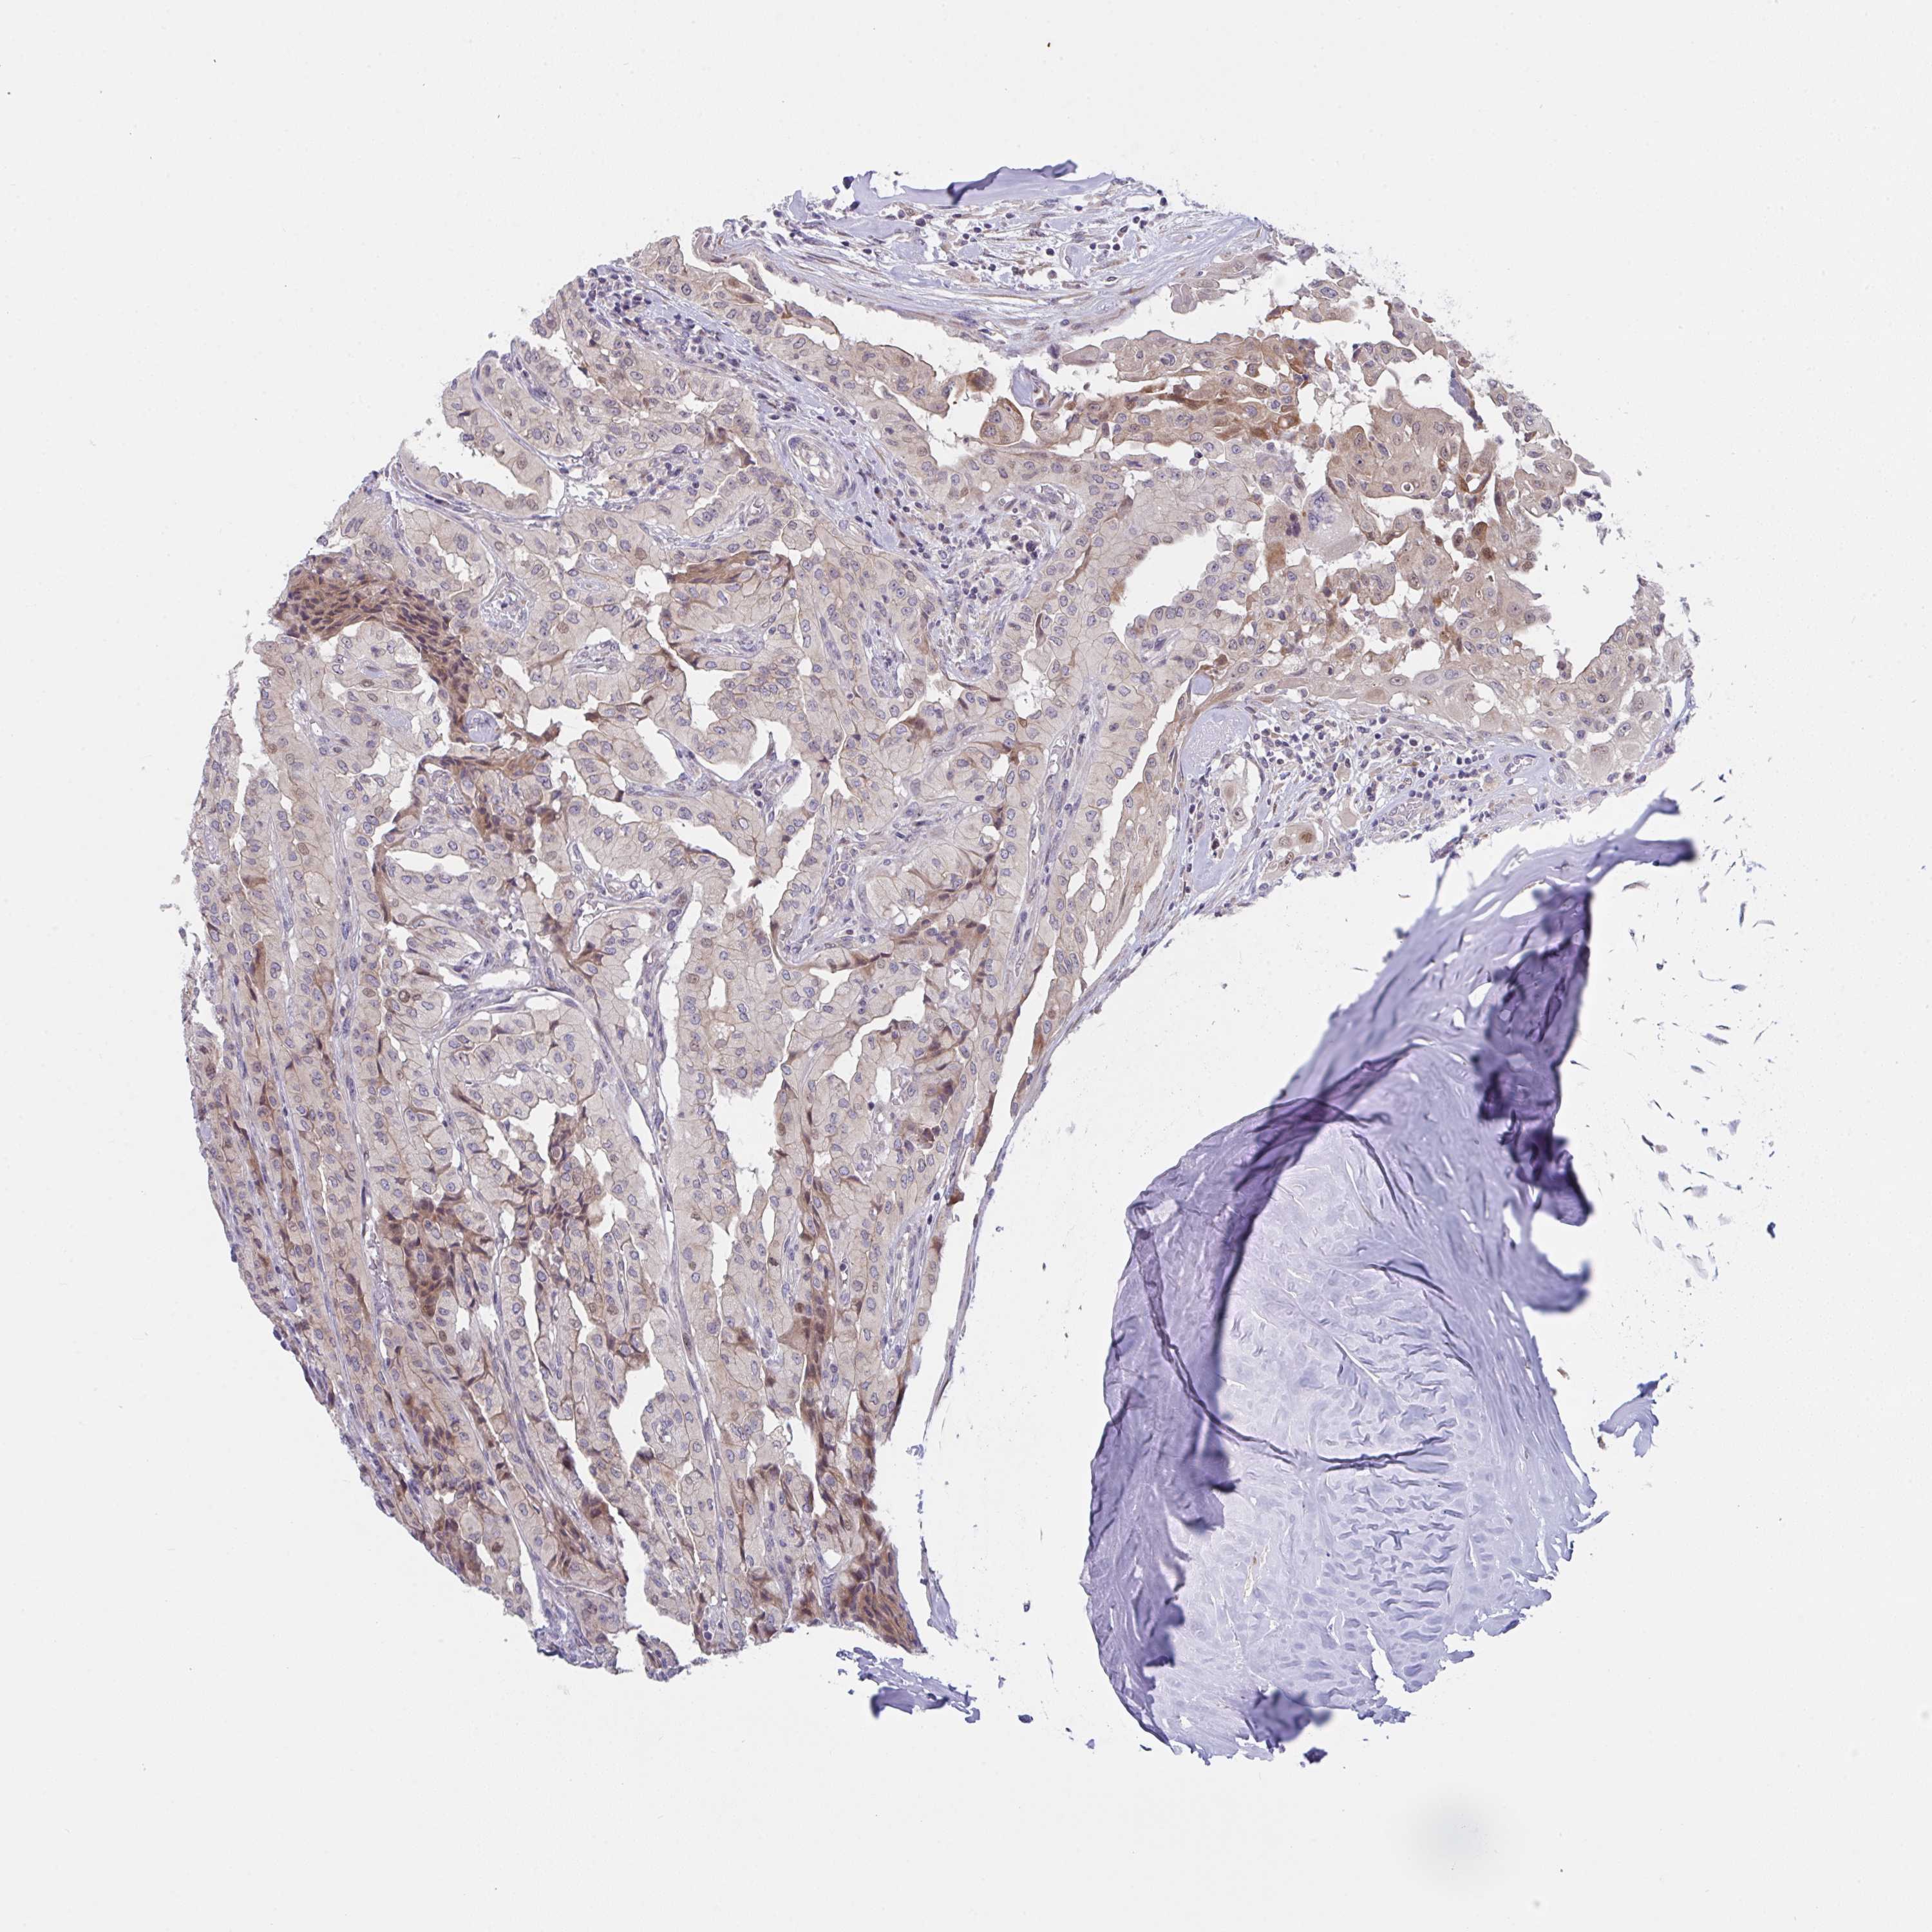

THYROID CANCER - Protein expressioni

A mouse-over function shows sample information and annotation data. Click on an image to view it in a full screen mode. Samples can be filtered based on level of antibody staining by selecting one or several of the following categories: high, medium, low and not detected. The assay and annotation is described here.

Note that samples used for immunohistochemistry by the Human Protein Atlas do not correspond to samples in the TCGA dataset.

Antibody stainingi

Antibody staining in the annotated cell types in the current human tissue is reported as not detected, low, medium, or high, based on conventional immunohistochemistry profiling in selected tissues. This score is based on the combination of the staining intensity and fraction of stained cells.

Each image is clickable and will lead to virtual microscopy that enables deeper exploration of all samples and also displays staining intensity scores, fraction scores and subcellular localization as well as patient and tissue information for each sample.

Antibody HPA057281

Papillary adenocarcinoma, NOS

Follicular adenoma carcinoma, NOS